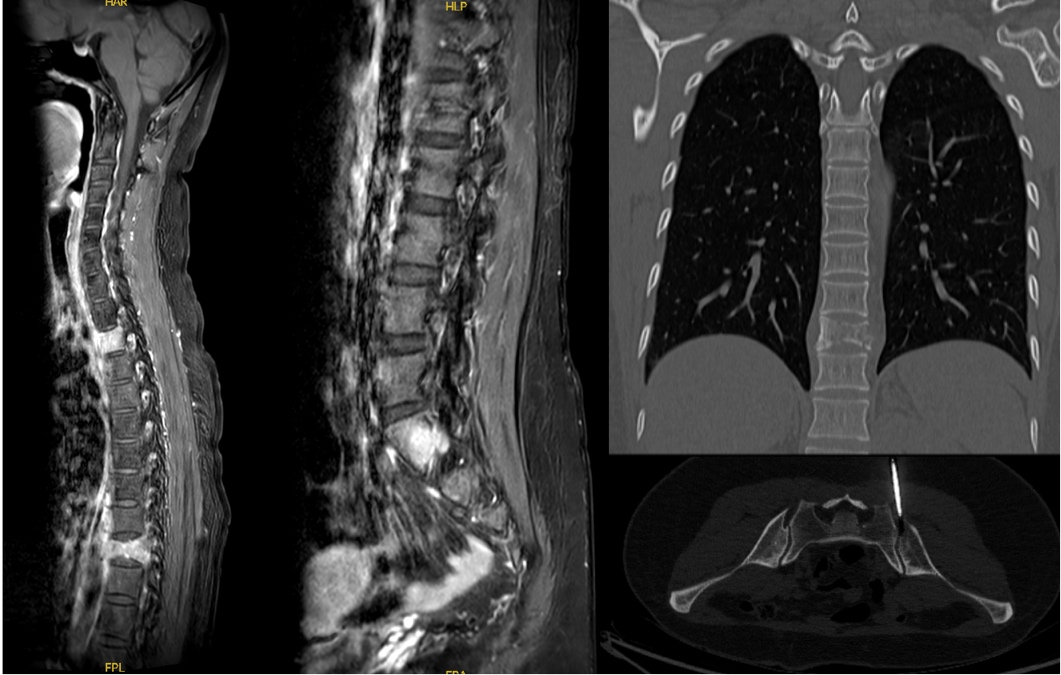

2025年5月胸腹盆CT及全脊柱MRI

脊柱多发转移瘤(T3、T10、L3椎体及附件,其中T10椎体合并病理性骨折)。左乳、肺、肝等未见明显异常。

转移灶放疗(2025-06-26至07-17)

脑转移瘤术腔+胸腰椎转移灶(T3-4、T9-10、L3-S1)姑息放疗(分次剂量300cGy,共16次)。